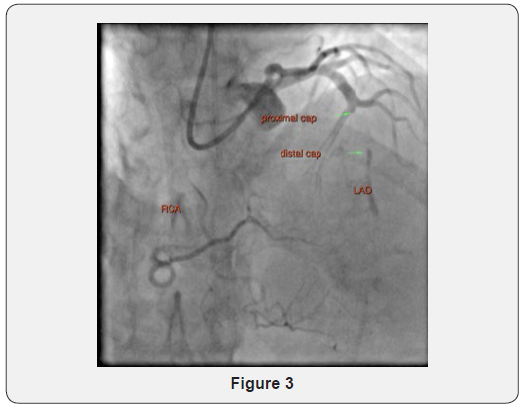

A second point of arterial access was obtained via the left distal radial artery with a second 6F Terumo Glide-sheath Slender and a 6 F ADROIT JR4 (Cordis) guide catheter was used to intubate the RCA to provide dual acquisition and revealed a J- CTO score 3- lesion at mid-LAD (Figure 3).